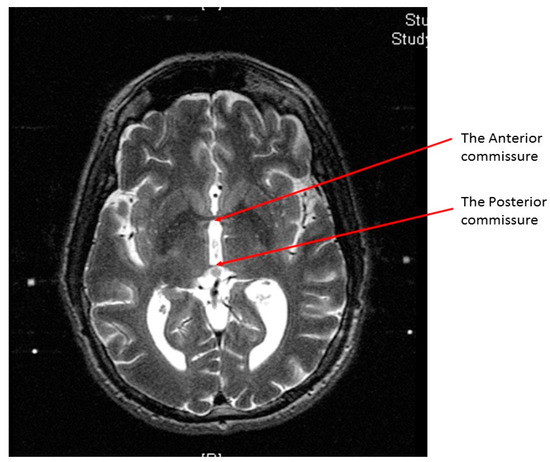

At the end of the scan, we chose an axial T2 image (or two adjacent images) in which both the AC and the PC are seen (Figure 3). With simple arithmetic equations based on the Leksell frame coordinates system, we were able to calculate the stereotactic coordinates of the mid-commissural point (MCP), and the STN directly from the MRI coordinates of the AC and the PC (Figure 4). Based on the known anatomical relationship of the STN to MCP from the previous anatomical studies and stereotactic atlases [36,47,48,49,50,51,52,53,54], we selected the STN target at 12 mm lateral, 3 mm posterior, and 6 mm inferior to the MCP.

Figure 4. Calculating the anterior commissure (AC) and posterior commissure (PC) coordinates using the magnetic resonance console. (A) Two diagonal lines intersecting at the center of the frame at the AC level with the magnetic resonance imaging (MRI) coordinates of the center of the frame shown inside the red square; (B) a crosshair at the posterior margin of the AC, with the MRI coordinates of the AC shown inside the red square. Two lines are drawn between the middle and the lower fiducials on both sides of the frame and their lengths (in the blue rectangle) are used to calculate the Z coordinate of the AC. (C) Two diagonal lines intersecting at the center of the frame at the PC level with the MRI coordinates of the center of the frame shown inside the red square; (D) a crosshair at the anterior margin of the PC, with the MRI coordinates of the PC shown inside the red square. Two lines are drawn between the middle and the lower fiducials on both sides of the frame and their lengths (in the blue rectangle) are used to calculate the Z coordinates of the PC.